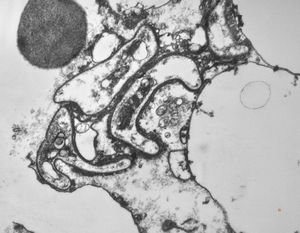

cytomegalovirus - pneumonia